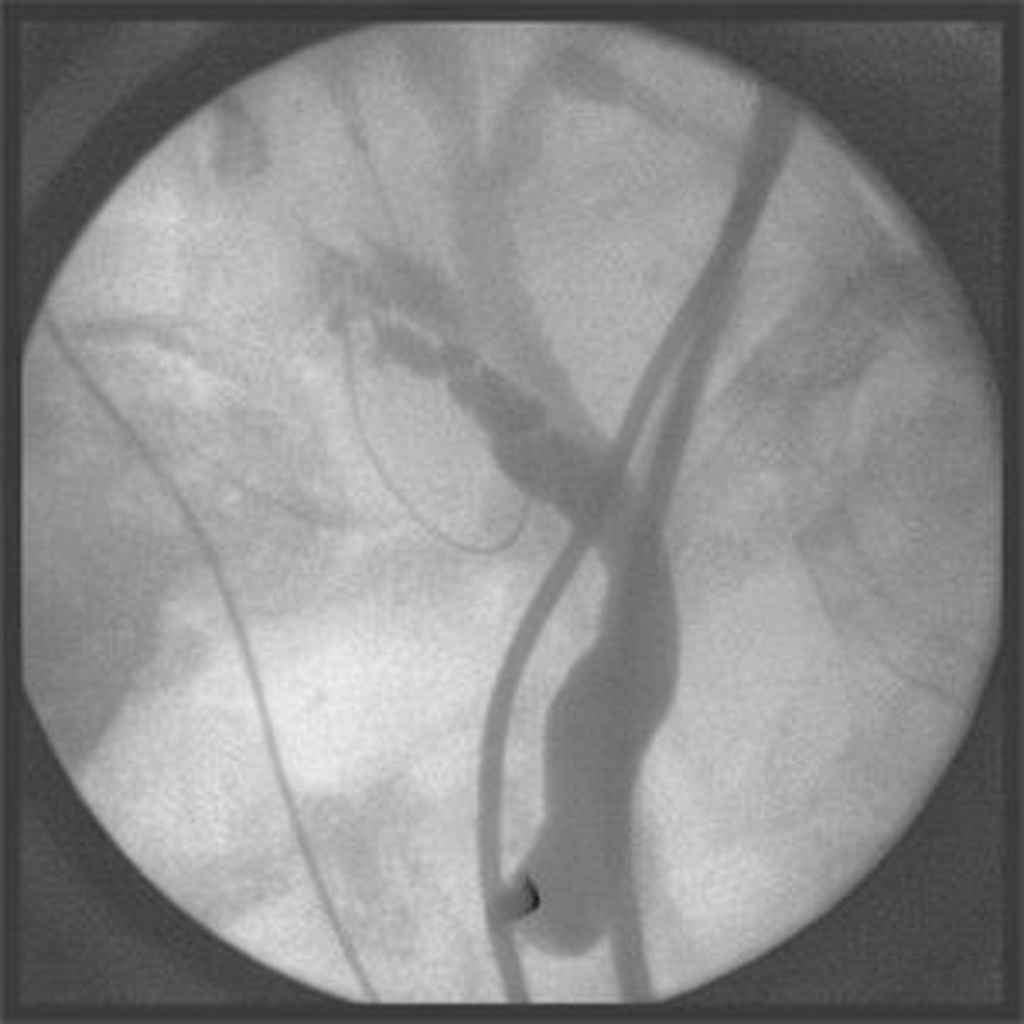

Explanation: **Explanation:** **Correct Answer: D. Egas Moniz** António Egas Moniz, a Portuguese neurologist, is credited with developing **cerebral angiography** in 1927. He successfully visualized the blood vessels of the brain by injecting radiopaque contrast (initially sodium iodide) into the carotid artery. This breakthrough allowed for the diagnosis of tumors, vascular malformations, and aneurysms, which were previously invisible on standard X-rays. For his contributions to neurology (specifically the development of leucotomy), he was awarded the Nobel Prize in 1949. **Analysis of Incorrect Options:** * **A. Sir Walter Dandy:** An American neurosurgeon known for developing **pneumoencephalography** (injecting air into the ventricles) and ventriculography. He was also the first to clip an intracranial aneurysm. * **B. George Moore:** He pioneered the use of **fluorescein** to localize brain tumors during surgery and was an early advocate for using radioactive isotopes in brain scanning. * **C. Seldinger:** Sven-Ivar Seldinger developed the **Seldinger Technique** in 1953. This is the standard method for percutaneous vascular access using a needle, guidewire, and catheter, which revolutionized interventional radiology but came decades after Moniz’s discovery. **High-Yield Clinical Pearls for NEET-PG:** * **Father of Angiography:** Egas Moniz. * **Seldinger Technique Steps:** Needle → Guidewire → Remove Needle → Dilator/Catheter over wire → Remove wire. * **Contrast Media:** Modern angiography uses non-ionic, low-osmolar iodinated contrast (e.g., Iohexol) to reduce the risk of nephrotoxicity and allergic reactions. * **Pneumoencephalography:** Historically used for visualizing the ventricular system but has been entirely replaced by CT and MRI.

Angiography Techniques